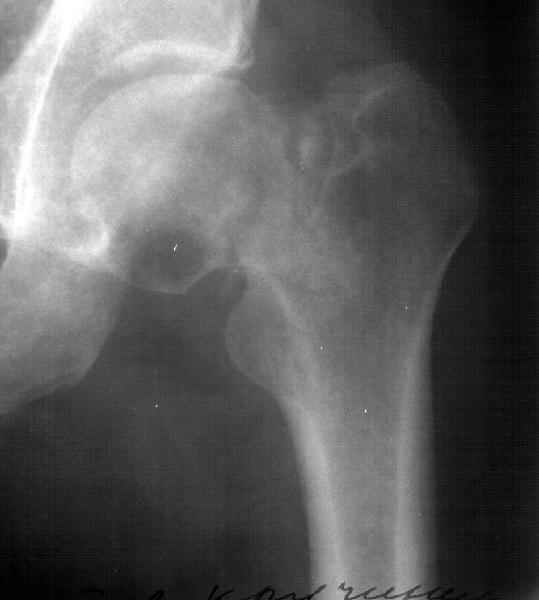

Уважаемый Александр! По 38-летнему пациенту. На томограмме имеются явные признаки асептического некроза. Этот процесс будет развиваться стремительно.

1-2 года и Вы вынуждены будете эндопротезировать пациента. Есть ли необходимость в дополнительной операции (остеотомии)? У 35-летнего пациента

Коль скоро функция сустава сохранена, я бы не торопился с эндопротезированием у 38 летнего пациента.

Рентгенологические признаки пост травматического аваскулярного некроза по классификации Ficat / Arlet Stage 1. на мой взгляд DHS - без какой -либо остеотомии стабилизировало зону перелома, а сам процесс рассверливания шейки бедра съимитировал бы так называемую core decompression procedure, которая показана при 1-3 стадиях AVN.

At first is necesary take a Magnetic Resonance for the diagnosis de avascular necrosis.

I see zones of osteoporosis in the head and for this is necesary a vascular existence, then for me was necesary the MR.

You have a non union neck, avascualr necrosis and varus deformity.